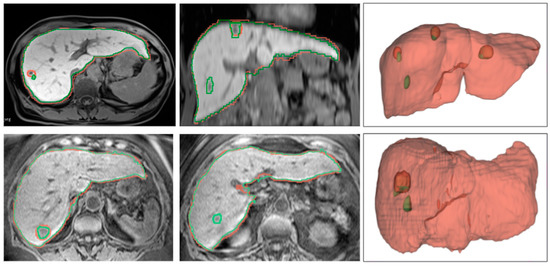

4.2.2. Qualitative Results